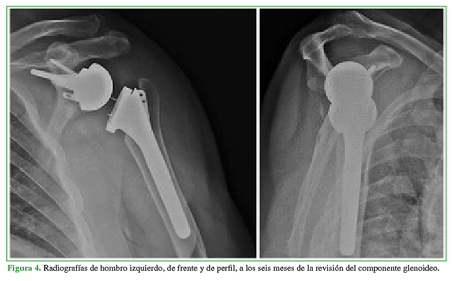

En las radiografías, se detectó que dos pacientes tenían muescas glenoideas grado I (Figura 3). No hubo casos de aflojamiento del componente humeral, sí se registró como única complicación mayor posoperatoria el aflojamiento mecánico del componente glenoideo en un paciente a los 14 meses de la cirugía inicial; en este caso, se procedió a la revisión con colocación de una glena de revisión (Figura 4). La tasa de supervivencia del implante fue del 97,5%.

Entre las fracturas intraoperatorias de glena, en una revisión sistemática, Zumstein y cols. comunicaron una prevalencia del 0,9% en 782 hombros, que estuvieron principalmente relacionadas con el fresado articular.13 Sirveaux y cols. tuvieron una prevalencia del 1,5% en 1953 AI, el riesgo fue mayor en ascenso severos de la cabeza humeral.11 El 5% de fracturas glenoideas en nuestra serie resulta levemente superior al reportado por Sirveaux y cols.11 Esto se justifica, en parte, por la curva de aprendizaje con este implante, que además se caracteriza por una resección ósea glenoidea más agresiva. Un paciente tuvo un aflojamiento mecánico del componente glenoideo a los 14 meses de la cirugía; esta complicación ocurre en el 1,8-8,8% de los casos.14,28 Pese a que aún no se han identificado factores de riesgo asociados, en su serie de 202 hombros tratados con prótesis lateralizada y una incidencia del 1,2% de esta complicación en cirugías primarias, Bitzer y cols. identificaron como factores de riesgo el uso de injerto óseo para suplir defectos glenoideos y la fijación del baseplate con tornillos no bloqueados.14 En nuestro paciente, el aflojamiento se debió a una toma insuficiente de los tornillos glenoideos, que fue tratado luego con una metaglena de revisión; el paciente cursa el sexto mes posoperatorio sin complicaciones agregadas.